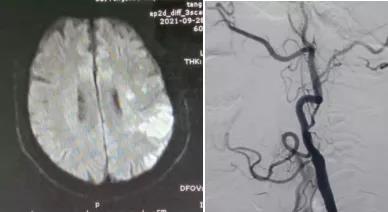

患者男,66歲,因“言語不清1天”于9月27日由外院轉(zhuǎn)入我院。既往“高血壓病”病史10余年,“冠心病心絞痛”病史2年。患者入院后頸部血管彩超檢查示:左側(cè)頸內(nèi)動(dòng)脈閉塞;腦MRI檢查示:左側(cè)半球急性腦梗死。10月5日行全腦血管造影檢查示:左側(cè)頸內(nèi)動(dòng)脈起始處閉塞。考慮患者有急性梗死,血管再通治療容易出現(xiàn)過度灌注綜合征引起腦出血,建議3周后行閉塞再通治療。

10月27日,在局部麻醉下行介入再通治療,腦血管造影示左側(cè)頸內(nèi)動(dòng)脈起始處閉塞,微導(dǎo)絲攜1.5*2mm球囊多次嘗試,成功通過閉塞段,給予球囊擴(kuò)張,擴(kuò)張后造影見有細(xì)血流通過,保護(hù)傘緩慢通過狹窄段,釋放保護(hù)傘,給予4*20mm球囊再次擴(kuò)張,然后植入閉環(huán)支架一枚,造影示血流通暢,顱內(nèi)血管顯影良好,再通成功,結(jié)束手術(shù),患者無不適,3天后出院。